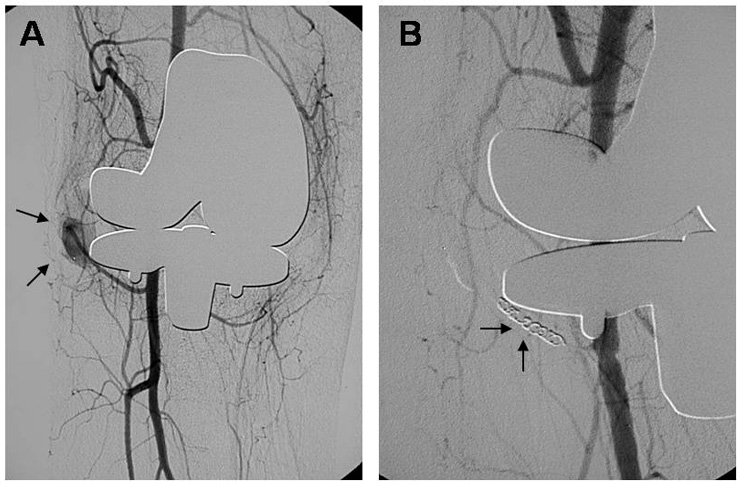

Figure 3

Angiographic photographs showing a false aneurysm of the inferior medial popliteal artery of the right knee (a) before and after intervention via coiling (b).

On the eleventh postoperative day the patient complained of new and severe pain in the right knee. Ultrasound with duplex colour Doppler suggested the diagnosis of false aneurysm. Digital subtraction angiography (DSA) showed a false aneurysm arising from the inferior medial genicular artery into the knee joint (fig. 3). The morphology of the vascular appearance suggested a pseudoaneurysm formation with irregular saccular form dilatation of the artery. Irregularities of the adjacent synovial arterial vessels were also evident. Under protection of rFVIIa embolisation was performed successfully with no additional complication.

As a fast screening method ultrasound with duplex colour Doppler was performed and suggested the formation of a false aneurysm. As suggested by Mann et al. [29], the authors performed a DSA clearly revealing a false aneurysm arising from the inferior medial genicular artery, and obtained rapid embolisation using metal coils [30]. With the knowledge of this case, the authors suggest that angiography before implantation of a total knee prosthesis in haemophilic arthropathy could be performed routinely [23, 27, 28]. If sudden pain in the knee occurs after TKA one should bear in mind possible false aneurysm formation or other vascular complications.